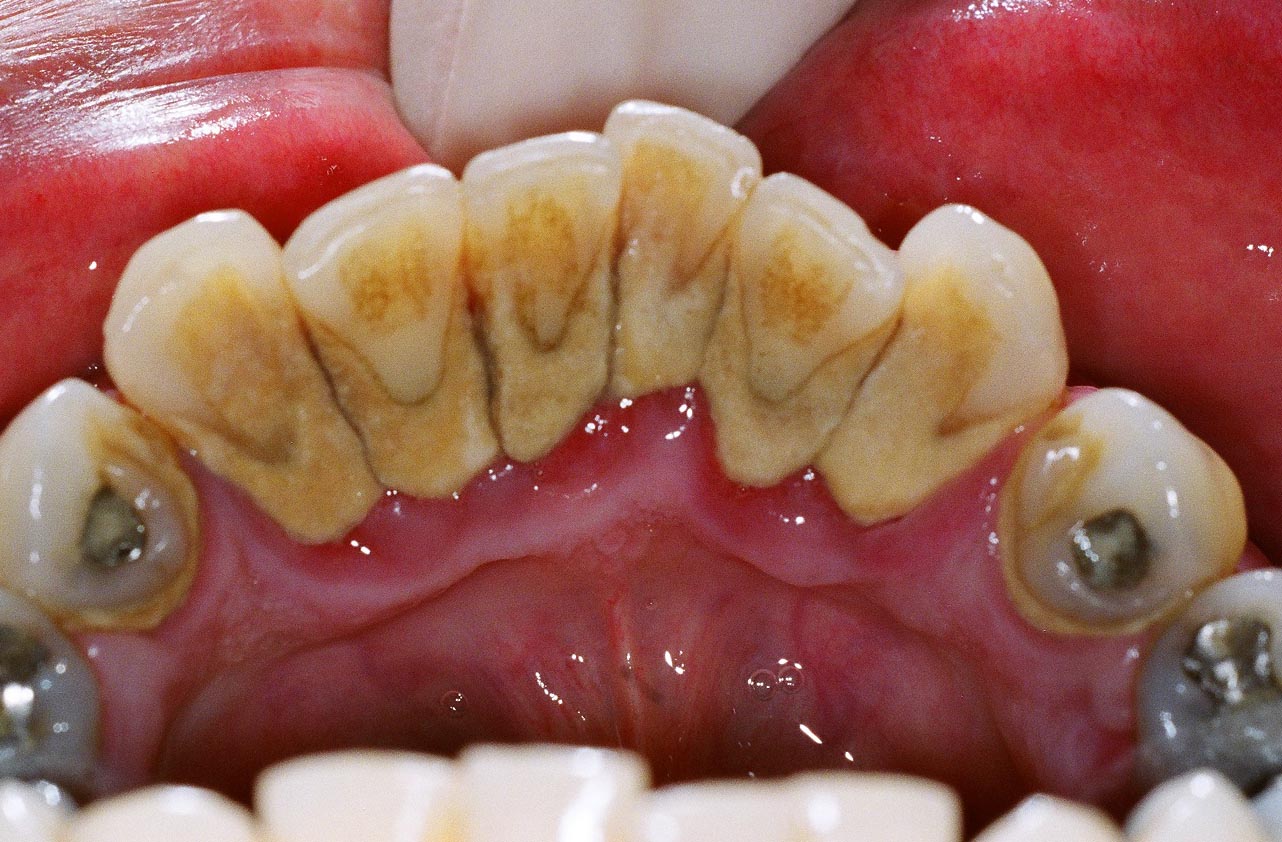

| Plak atau kotoran gigi menyebabkan gusi di daerah

leher gigi meradang. Perhatikan bahwa gusi di dekat plak gigi lebih

merah dan bengkak dibandingkan daerah gusi di bawahnya. Pada kondisi

ini, gusi sangat mudah berdarah bahkan hanya dengan sentuhan ringan

misalnya saat makan makanan yang agak keras atau saat menyikat gigi. |

Plak akan "matang" setelah 1-2 hari tanpa penyikatan gigi sama sekali, dan mengandung material organik seperti lemak, protein dan enzim serta material anorganik yaitu mineral terutama kalsium dan fosfor. Plak yang menumpuk dapat menyebabkan peradangan pada gusi, akibatnya gusi bengkak, warnanya merah terang, dan mudah berdarah. Kondisi ini juga dapat menyebabkan bau mulut karena plak akan diolah oleh bakteri dan menghasilkan senyawa sulfur yang menjadi sumber bau tak sedap.